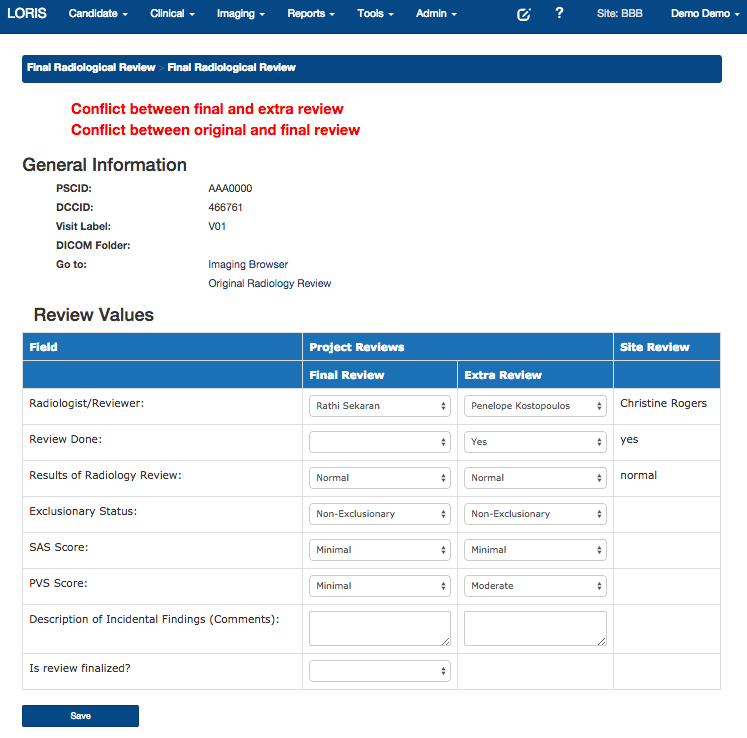

Radiological Review Module, DCC MRIData Querying

- Radiological Reviews - Visualization, including module to curate